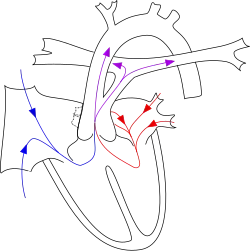

A well-known classification is the fourfold system developed by Collett and Edwards in 1949.[9] Collett/Edwards Types I, II, and III are distinguished by the branching pattern of the pulmonary arteries:[10][11]

- Type I: The branch pulmonary arteries arise from a single "main pulmonary artery" arising from the lateral surface of the common trunk

- Type II: The branch pulmonary arteries arises separately, but near each other posteriorly off the common trunk

- Type III: The branch pulmonary arteries arise separately and far apart off the common trunk

- Type IV: The branch pulmonary arteries arise distally off the aorta, or the lungs are supplied by multiple aortopulmonary collaterals. Type IV is now considered a form of Tetralogy of Fallot and not Common Arterial Trunk.[11]

Another well-known classification was defined by Stella and Richard Van Praagh in 1965.[11][12] In this classification scheme, the preceding letter ("A" or "B") refers to the presence or absence, respectively, of a ventricular septal defect. Type B common arterial trunk is extremely rare; so below, only Type A is considered:

- Type A1: The branch pulmonary arteries arise from a single "main pulmonary artery" arising from the lateral surface of the common trunk (Collett & Edwards Type I)

- Type A2: The branch pulmonary arteries arise separately off the common trunk (includes both Collett & Edwards Types II and III).

- Type A3: One branch pulmonary artery arises off the common trunk, and one branch pulmonary artery is isolated, arising from a patent ductus arteriosus.

- Type A4: Common arterial trunk in association with interrupted aortic arch.